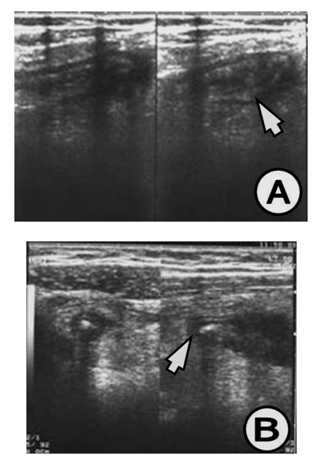

The appendix on US study is demonstrated by: hypo echoic lumen, hyper echoic mucosa, iso echoic lamina propria, hyper echoic submucosa, hypo echoic muskularis and hyper echoic serosa. The increased size of the appendix is a sign for phlegmonous or gangrenous appendicitis (Figure 1). The present appendicolith is demonstrated as hyper echoic mass that fills in the lumen and gives acoustic shadow (Figure 2B). When the appendicolith should be visualized, the wall thickness and the compressibility are not the features for making the diagnosis of acute appendicitis. The gangrenous appendicitis has changes in echogenity in all layers and the same are with the uniform echogenity and cannot be distinguished (Figure 3A). If the ill defined or hypo echoic mass is seen that surrounds the appendix that presents the periappendiceal inflammation (Figure 4). The ill defined appendiceal wall is suggestible, but not diagnostic for the periappendiceal process. The fluid presence into the appendiceal surrounding, with appendiceal wall echogenity changes is US feature for perforation (Figure 3B). The positive lymph nodes are oval hypo echoic and they don’t change the shape on compression.

Figure 1 (A) Appendix increased in size, 17 mm in diameter, thickened wall greater than 6 mm, (B) Appendix with widened lumen with dense contents, with 18 mm in diameter and thickened wall greater than 5 mm. US finding for appendiceal phlegmon.